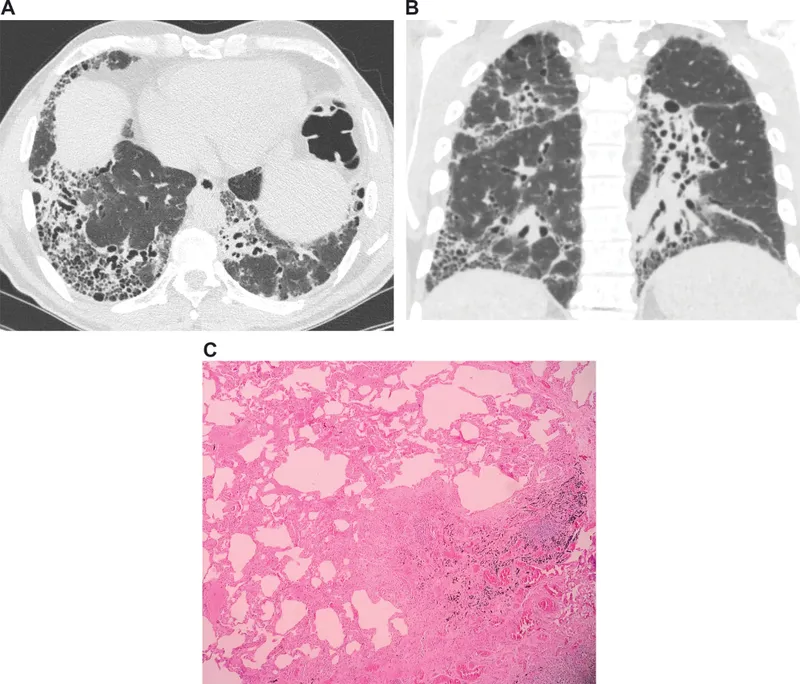

- Idiopathic Pulmonary Fibrosis (IPF): "honeycombing" on CT.

- Pathology: Histological pattern is Usual Interstitial Pneumonia (UIP).

- Patchy, peripheral, subpleural fibrosis.

- Temporal heterogeneity: areas of established fibrosis (collagen) adjacent to early fibroblastic foci.

- Late stage: Honeycomb lung (cystic fibrotic airspaces).

⭐ Exam Favorite: The hallmark of UIP is spatial and temporal heterogeneity, meaning scarred and normal lung tissue coexist, reflecting ongoing, asynchronous injury.